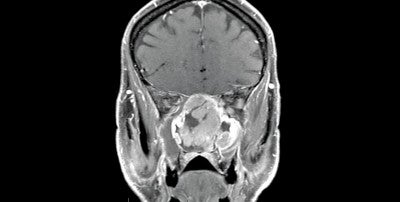

“My training emphasized endoscopic and minimally destructive approaches to the anterior and lateral skull base as well as the paranasal sinuses,” Parsel says. “The majority of my procedures are done endoscopically, through the nose, with no external incision, except in situations where tumors are larger and require open approaches, either through a craniotomy or transfacial approach.”